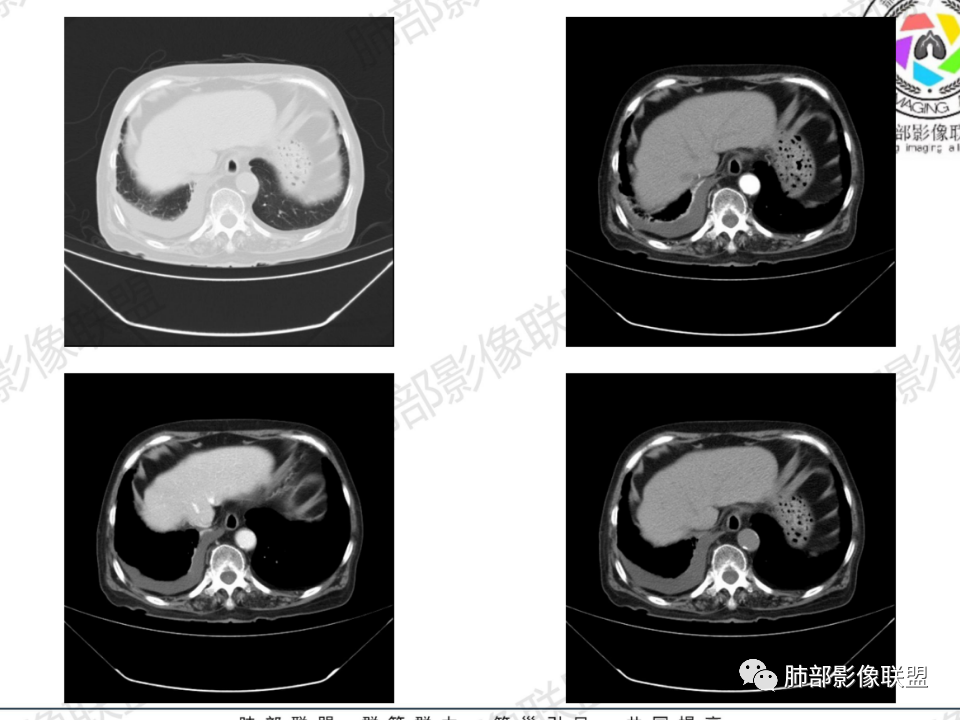

背段支气管周围增厚伴钙化,符合结核改变

胸腔积液并胸膜钙化,符合结核;

纵隔及双肺门见钙化淋巴结。心包积液,右侧胸腔积液(提示存在活动新病灶)。双侧胸膜下见多发斑点状钙化,胸廓变形(提示存在结核基础病变可能)。 诊断意见:综上,右肺上叶块状影更符合继发性肺结核。 最后小结:既往诊断淋巴结结核,提示已治愈。近2年服用激素,可疑诱导结核复燃,也可引起发热。纵隔肺门淋巴结肿大钙化,压迫支气管,右肺上中下叶支气管均狭窄,所以引起喘息咳嗽。尖段支气管受累闭塞,导致肺不张、支气管粘液栓,出现条状无强化区。病变累及胸膜,导致结核性胸膜炎并胸水,引起右侧胸痛。实验室检查血沉快,CA125高,低蛋白,均符合结核。下一步,建议支气管镜尖段支气管刷检并抗酸染色。(本段摘自於雄老师精彩发言)